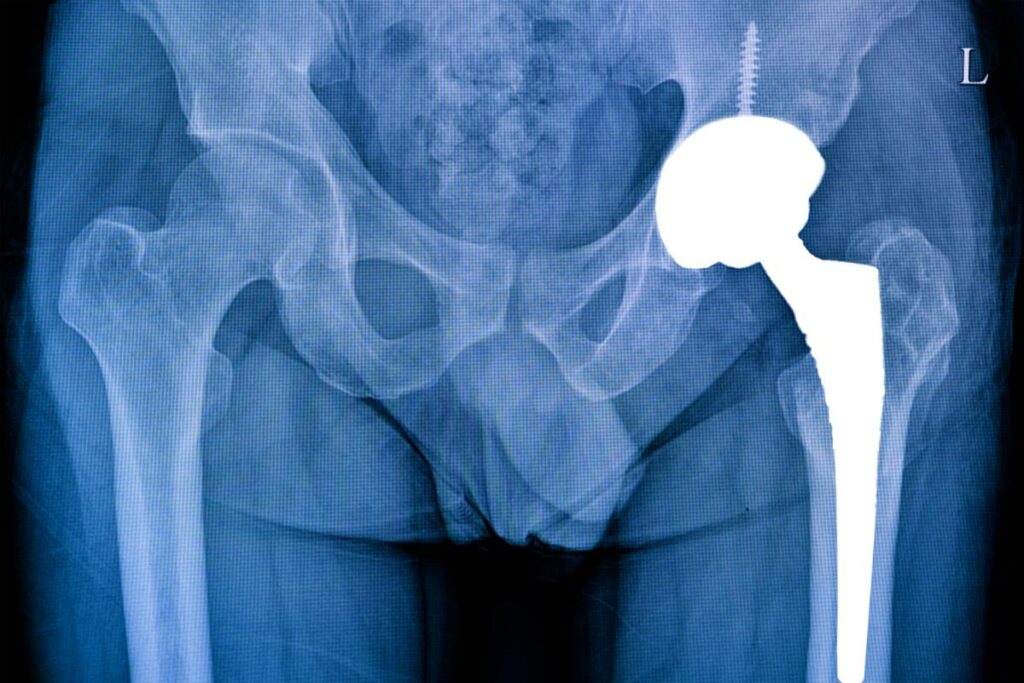

Una fractura de cadera es una rotura en la parte superior del hueso del fémur, el hueso más largo y fuerte del cuerpo. Esta lesión suele ocurrir en personas mayores debido a la osteoporosis, una enfermedad que debilita los huesos y los hace más propensos a romperse.

¿Cuál es el tratamiento?

El tratamiento dependerá del tipo de fractura, la edad del paciente y su estado general de salud. Las opciones incluyen:

• Tratamiento quirúrgico: Se utilizan placas, tornillos o prótesis para estabilizar la fractura.

• Tratamiento no quirúrgico: En algunos casos, se puede utilizar tracción o reposo en cama.